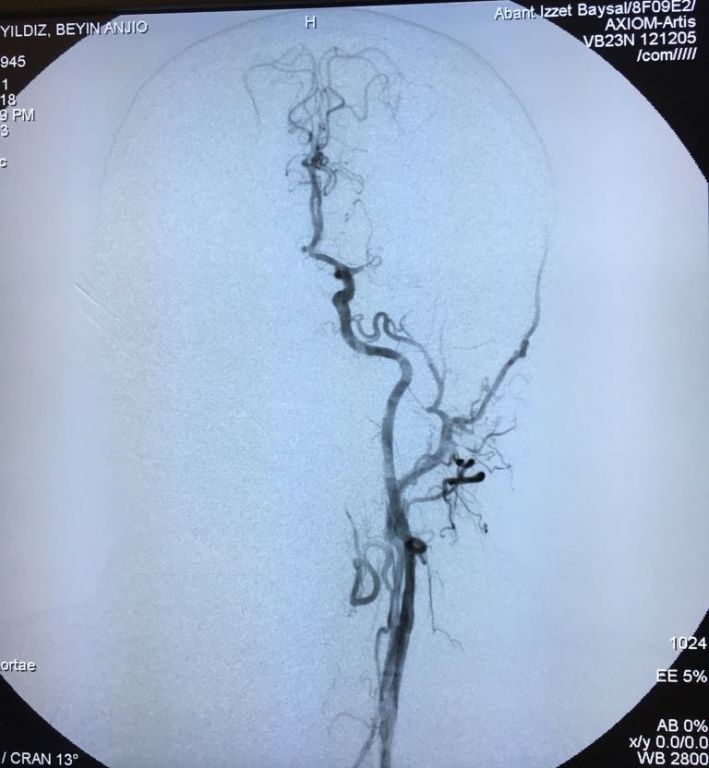

İzzet Baysal Eğitim ve Araştırma Hastanesinde yapılan işlemin aşamalarına ve tekniğine değinen Gürel; “Kanama gibi bazı riskler yoksa 1. aşama damardan pıhtı eritici ilaç vermek, ikinci aşama damarın içerisindeki pıhtıyı bir aletle çıkarmak. Hastanın hastaneye geldiği zaman ve ekip çok önemli. Hastanemizde ekip anlayışı içerisinde organizasyonumuzu kolaylıkla hızlıca yapabilmekteyiz.

Türkiye'de uygulanan 2 tip inme tedavisi şeklinin de hastanemizde uygulanabildiğini belirten Gürel; “İzzet baysal Eğitim ve Araştırma Hastanesi her iki hizmeti de vermeye başladı. Her yerde yapılamayan bu iki hizmeti ayrı ayrı ya da gerekli görüldüğünde aynı anda verebilecek kalitede son aşama hizmet vermekteyiz. Bu işlemlerle yatalak olacak hastayı hayata kazandırmış oluyoruz. Bu her hastada %100 başarı elde edeceğimizin kesin kararı değildir. Ancak bir ihtimal dahi olsa bu işlemi yapmaya değer. Ayrıca Bolu’da eğer biz bu hizmeti vermemiş olsaydık hastayı İstanbul ya da Ankara'ya götürdüğünüzde o bahsettiğimiz kritik zamanı yolda geçirmiş olacaktı ve işlemler için geç kalınacaktı.” dedi.